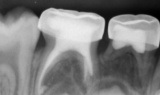

Συχνά σε νεογιλά δόντια που είναι αρκετά χαλασμένα η τερηδόνα (μικροβιακή μόλυνση) φτάνει ως το νεύρο του δοντιού. Σε αυτές τις περιπτώσεις και ανάλογα με την «έκταση» της μόλυνσης υπάρχουν δύο επιλογές, αυτή της πολφοτομής (μισής απονεύρωσης) και αυτή της ενδοδοντικής θεραπείας (πλήρους απονεύρωσης) του νεογιλού δοντιού.

Κατά την πλήρη ενδοδοντική θεραπεία αφαιρείται όλο το νεύρο, το δόντι καθαρίζεται και τοποθετούνται στο εσωτερικό του βιοσυμβατά υλικά που απορροφούνται μαζί με τις ρίζες του νεογιλού δοντιού όταν είναι να αλλαχθεί.